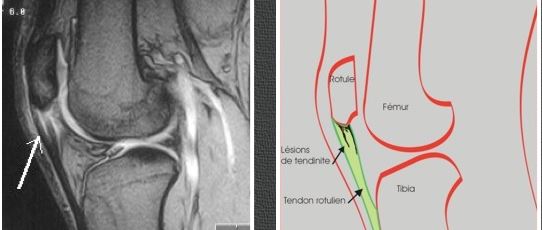

La Place De La Chirurgie Dans Le Traitement Des Tendinites Rotuliennes

Http Www Genou Douloureux Com Pdf Tendinite Anterieure De L Appareil Extenseur Du Genou Pdf

Ruptures De L Appareil Extenseur Du Genou Revue Medicale Suisse